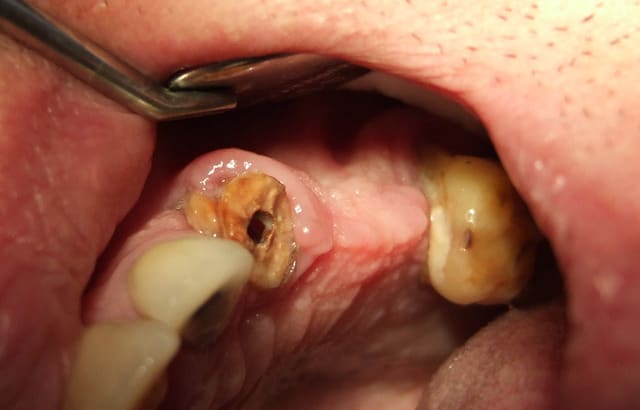

Voici la photo de la gencive une fois le bridge déposé..

(je ne suis pas un pro de la photo, on fait comme on peut quand on débute..)

Bilan long cône indispensable car c'est sûr, vu le peu que je vois sur cette photo, il y a une paro.